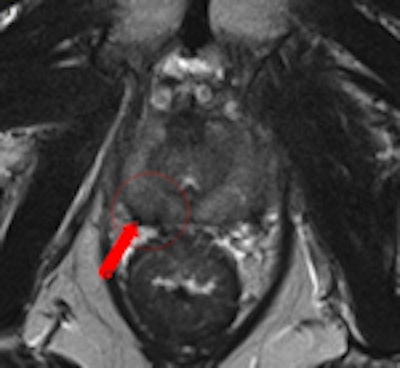

A 69-year-old male three years post electron-beam radiation therapy (EBRT, primary PC: Gleason 4+3 right PZ) with PSA increase to 2. MRI and TRUS-guided biopsy of this area confirmed Gleason 4+4 recurrence at right PZ (old tumor location). Left: Axial T2-weighted MR image shows low signal prostate due to previous EBRT. Therefore, tumor (arrow) is difficult to see. At arrow, there is some "bulging" (PI-RADS 5). Center: Axial DCE-MRI shows increased focal asymmetric contrast leakage at right PZ (circle, PI-RADS 5). Right: Axial ADC-map of DWI-MRI shows restriction (low signal, circle, PI-RADS 5). Final diagnosis: PI-RADS 5. TRUS biopsy of this area confirmed Gleason 4+4 recurrence."Prostate imaging at 3-tesla benefits from higher signal-to-noise ratio and enables high-quality imaging within a short time without the use of an ERC [endorectal coil]. Data on 3-tesla for prostate cancer MRI are still conflicting. Thus, further research on this topic is needed," the authors noted. "Limitations of 3-tesla MRI are shorter T2- and longer T1-relaxation times, problems with susceptibility artifacts, dielectric effect, specific absorption rate, and the homogeneity of the magnetic field. However, hardware, multichannel coil, and parallel imaging technique improvements are currently solving most of these problems."